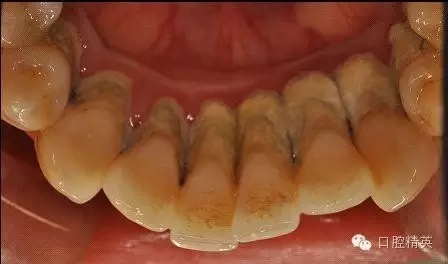

本病例 :女 34歲,主訴刷牙出血,覺(jué)牙齒輕度松動(dòng)一年。

檢查見(jiàn)大量齦上及齦下結(jié)石,探診出血,牙周袋較深,32-42 II度松動(dòng)。X線片顯示牙槽骨水平吸收。

治療前:

齦下刮治術(shù)(subgingival scaling),即根面平整術(shù)(root planing),是用比較精細(xì)的齦下刮治器刮除位于牙周袋內(nèi)根面上的牙石和菌斑。做齦下刮治時(shí),醫(yī)生會(huì)使用一些專(zhuān)用去除袋內(nèi)結(jié)石的器械,刮除袋內(nèi)結(jié)石、細(xì)菌和受細(xì)菌感染組織。由于進(jìn)行該項(xiàng)操作需將器械伸入袋的深部組織內(nèi),既要刮盡齦下牙石(有時(shí)還要刮除牙根表面的壞死組織),又要盡量避免多損傷牙周組織。這就需要有較高的技巧,只有經(jīng)過(guò)專(zhuān)門(mén)訓(xùn)練的專(zhuān)業(yè)技術(shù)人員才能完成。